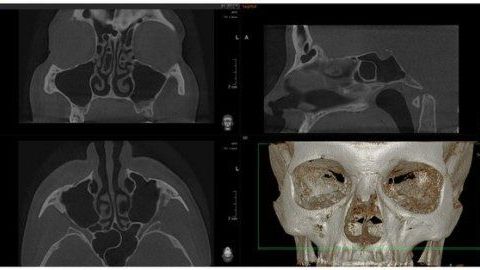

Один из самых информативных рентгеновских способов качественной диагностики заболеваний челюстно-лицевого аппарата. В результате КЛКТ врач получает 3D изображение исследуемого участка. Использование КЛКТ в стоматологии, лицевой хирургии позволяет обнаружить отклонения, поставить точный диагноз и назначить необходимое лечение

• Сканирование за 8,9 сек

• Полная 3D проекция – менее чем за 20 сек

• Снимает анатомические детали без искажений

•  3D сканирование на 360 градусов охватывает

оральные и лицевые области

• Стандартное изображение челюсти размерами 8

см в диаметре и высотой 8 см используется для

планирования имплантаций, эндодонтического

лечения и хирургических вмешательств

• Расширенное сканирование с изображением

размерами в 14 см диаметром* 8 см высотой

применяется для обследования челюстных суставов и

дыхательных путей